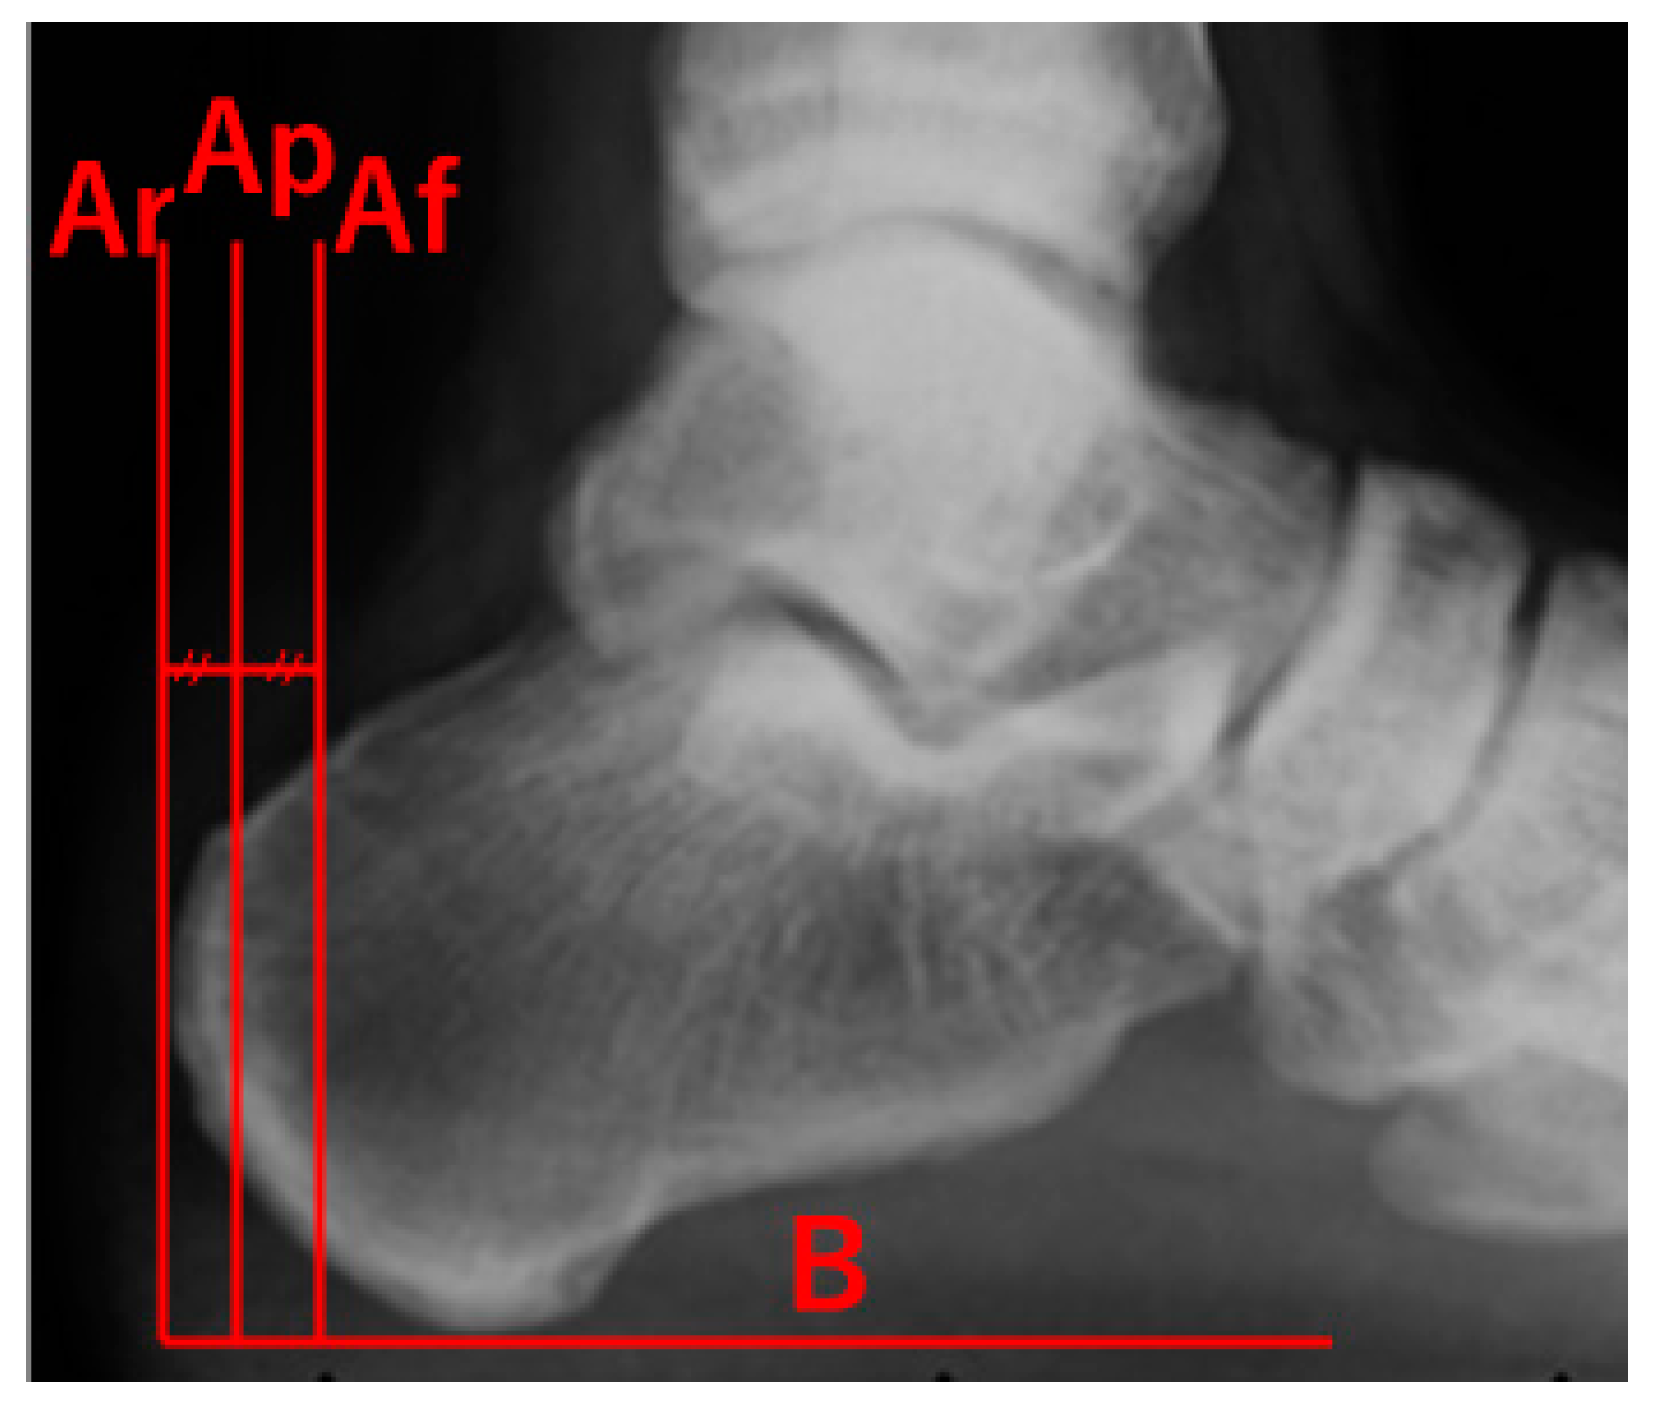

Effects of Achilles Tendon Moment Arm Length on Insertional Achilles Tendinopathy